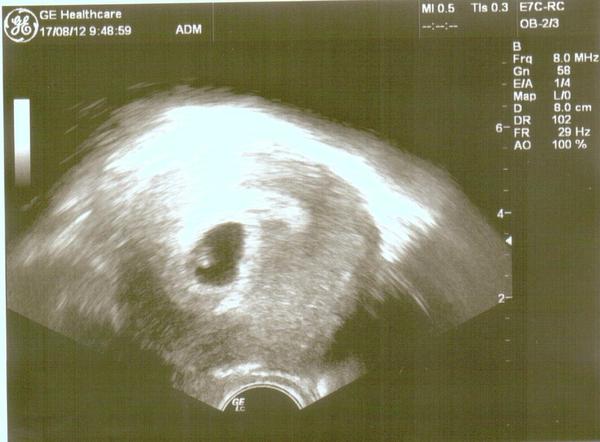

@pawlla na fotečce to asi nebude tak poznat,ale krásně jsme vyrostli 😉 a pěkně tam fazolka řádila 😀 to bude nějaký hyperaktivní 😀 ...dokonce nám tam něco pěkně problikávalo-podle dr.to bylo srdíčko,ale prý se teprve tvoří v tuto dobu..další kontrola v pátek.opět jsem dostala píchanec a v úterý si mám píchnout zas

@saraha2 to je skvely! Fotecka krasna! Vic takovych 😉 a kdy jdes znovu?